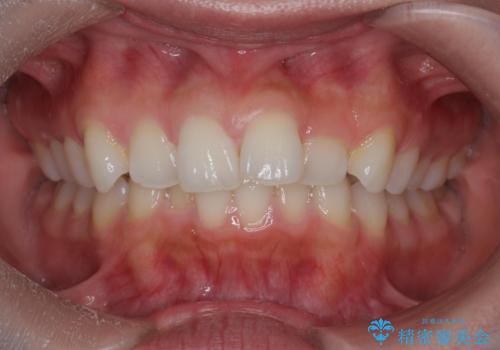

前歯のがたつき気になる。インビザラインモデレート

- 前歯のがたつきが気になるとの事で来院。

噛み合わせを確認したところ上の歯が全体的に前にある状態でした。

患者様は2のプランを選ばれたのでインビザラインモデレートで治療を行いました。